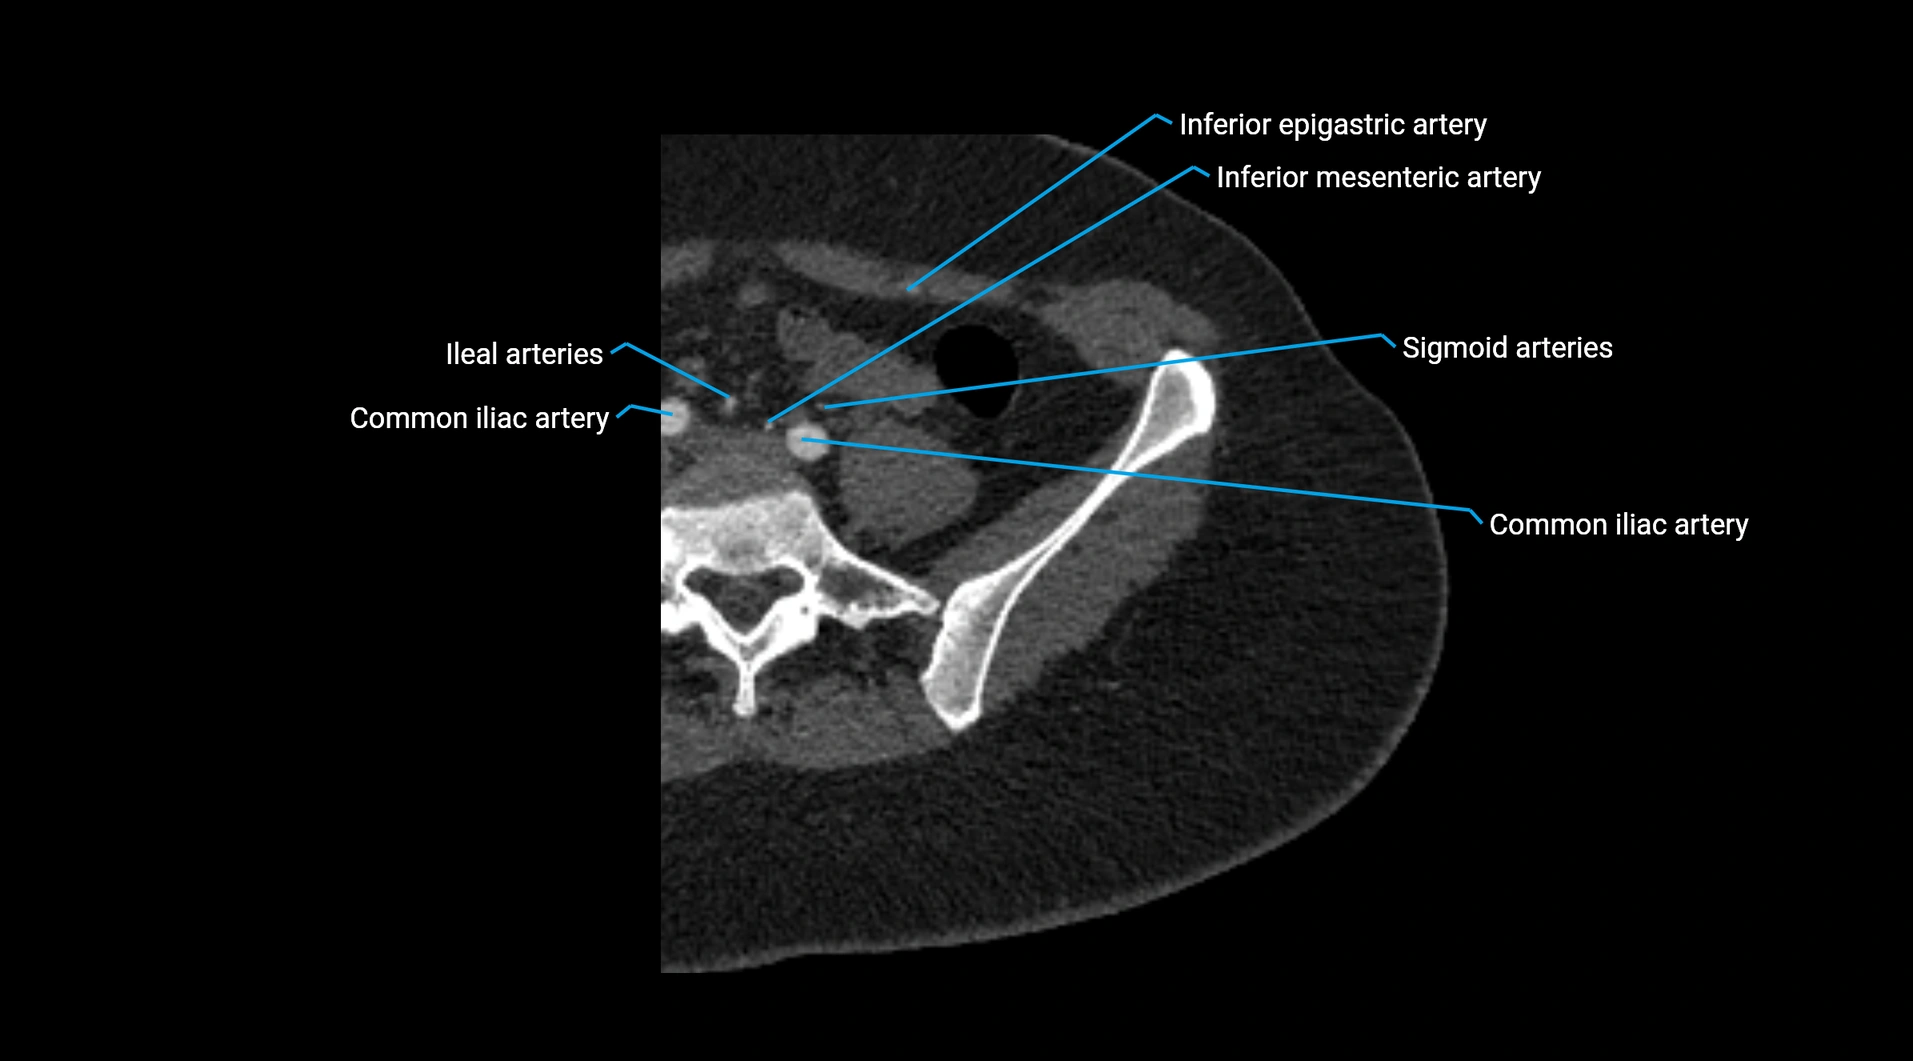

CT images

image